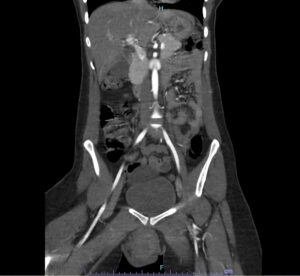

Vulvar Hematoma. CT Coronal, Unannotated. JETem 2024

Vulvar Hematoma. CT Coronal Unannotated. JETem 2024